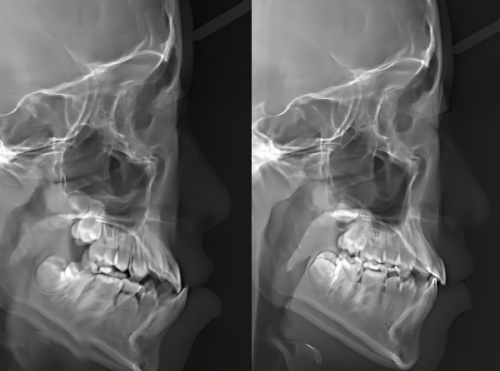

全博口腔非常注重引进国内外现代化的诊疗设备和技术。例如,引进了德国卡瓦种植机、美国隐适美隐形矫正系统等高端设备。这些设备的引进,为患者提供了更加个性化、科学有效的治疗方案。

精良的设备不仅提高了医生的工作精度,还让患者的治疗过程更加舒适、风险更低。比如在种植牙手术中,德国卡瓦种植机能够更精细地定位和操作,提高种植的成功几率;美国隐适美隐形矫正系统则让牙齿矫正更加美观、舒适,减少了患者在矫正过程中的不适感。